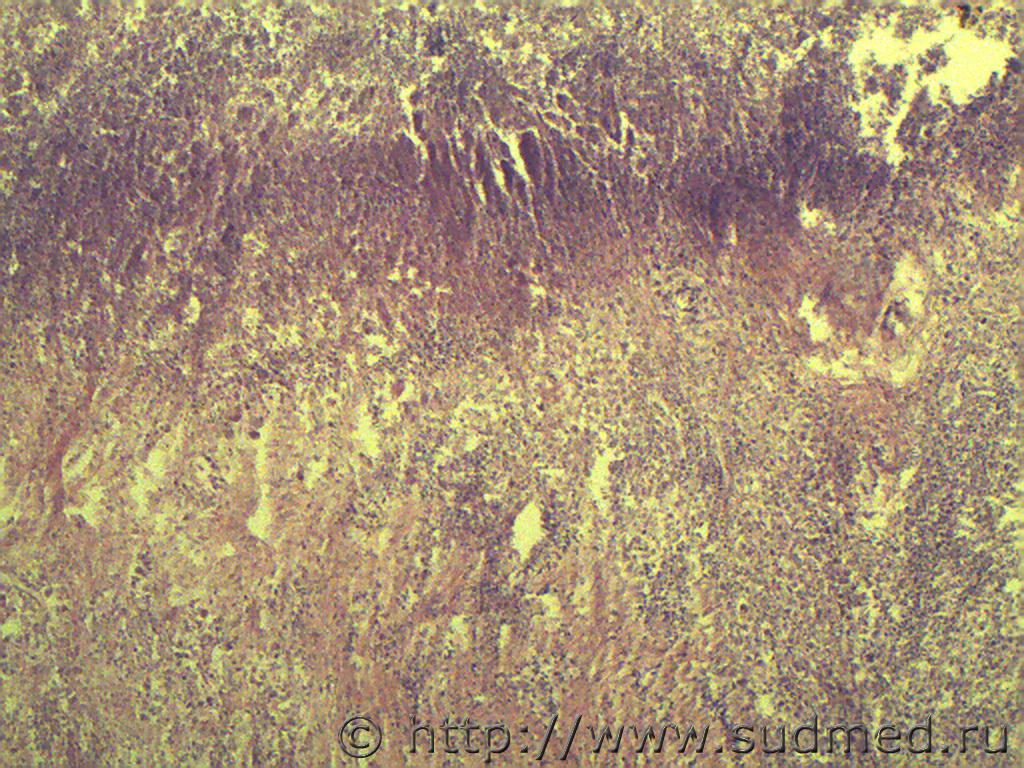

Язва-рак желудка.